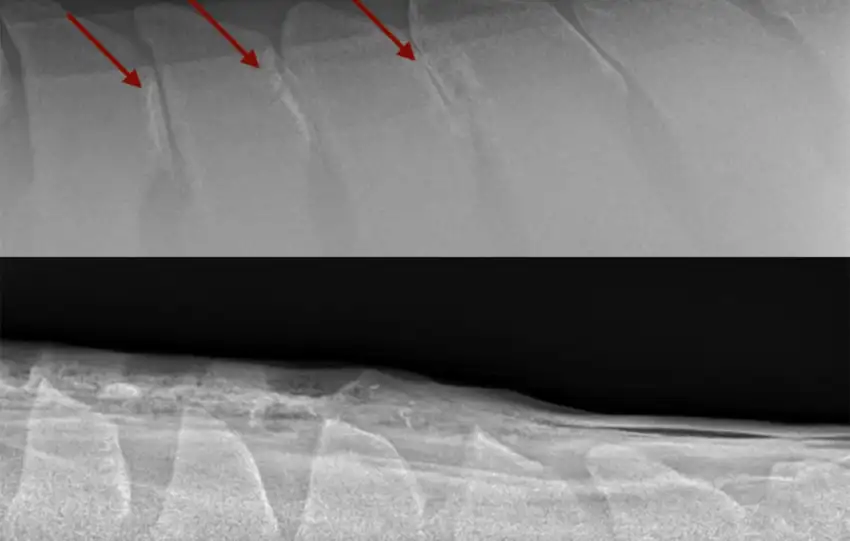

hat does it mean when people say a horse has “kissing spines”? The term kissing spines refers to the impingement or overriding of the dorsal spinous processes of the thoracolumbar vertebrae. In order to understand this, let’s review some anatomy.